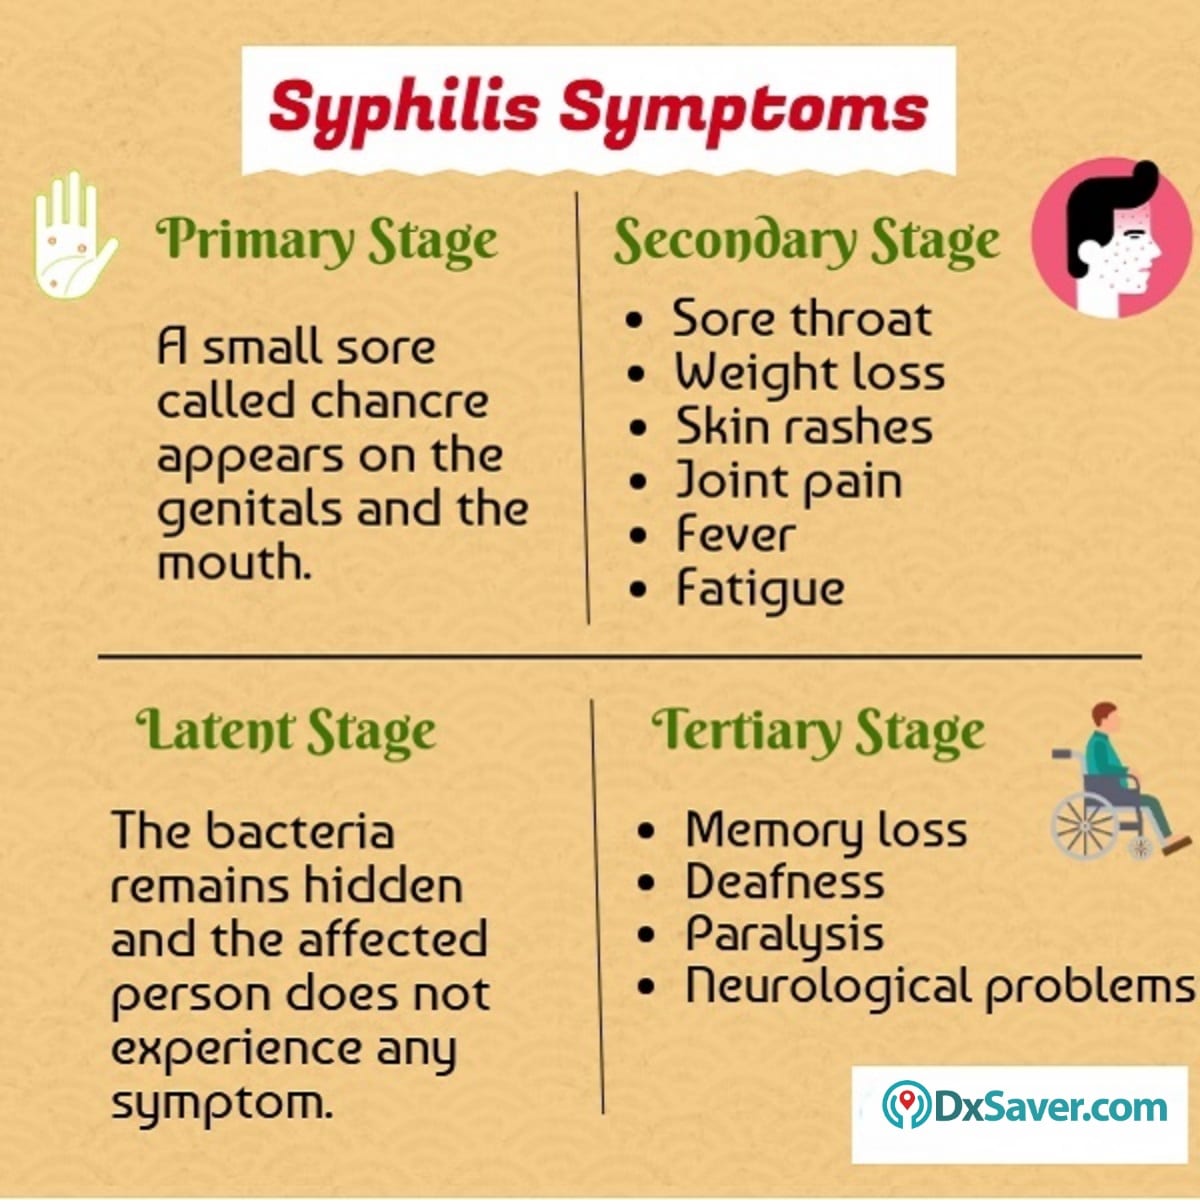

Stages of Syphilis: Symptoms, Causes, Prevention, and Treatment

Syphilis

Signs and Symptoms – syphilis-the great imitator

Syphilis